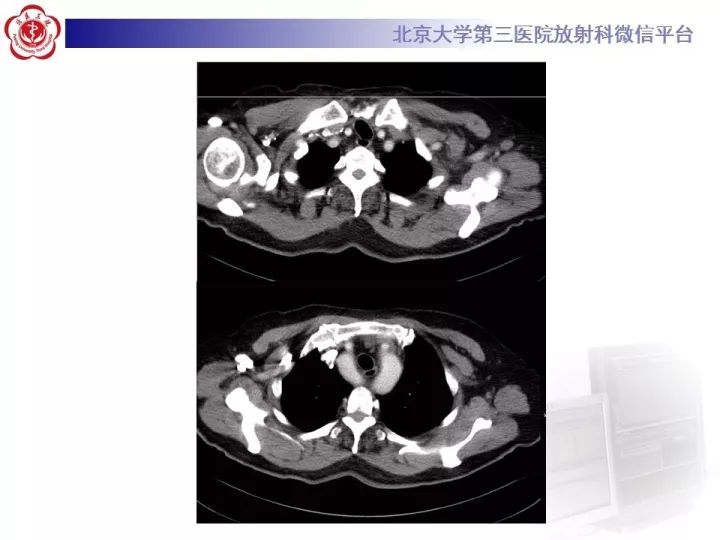

【病例】双主动脉弓畸形1例CT